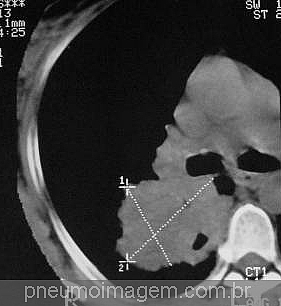

Para ver imagens de câncer de pulmão no PneumoImagem, clique aqui.